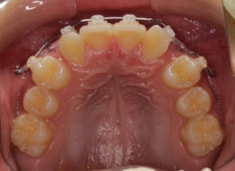

治療法:上顎急速拡大装置+クリアスナップ+フェイスマスク+上顎3番は開窓牽引CT写真にて位置確認

上下顎のギャップはありますが、顔面自体の幅径は良好な値を示していますので、スペース不足は拡大することによって解決できポテンシャルはあると考えられます。

検査時のレントゲン分析では、上下顎の関係は、上顎の劣成長があり下顎前突傾向という値がでておりましたが、前歯ジャンプ後はフェイスマスクの効果もあり、上下顎の関係は正常化しています。

上顎が若干優位になっていますので、今後の下顎の成長のための貯金になっているくらいです。